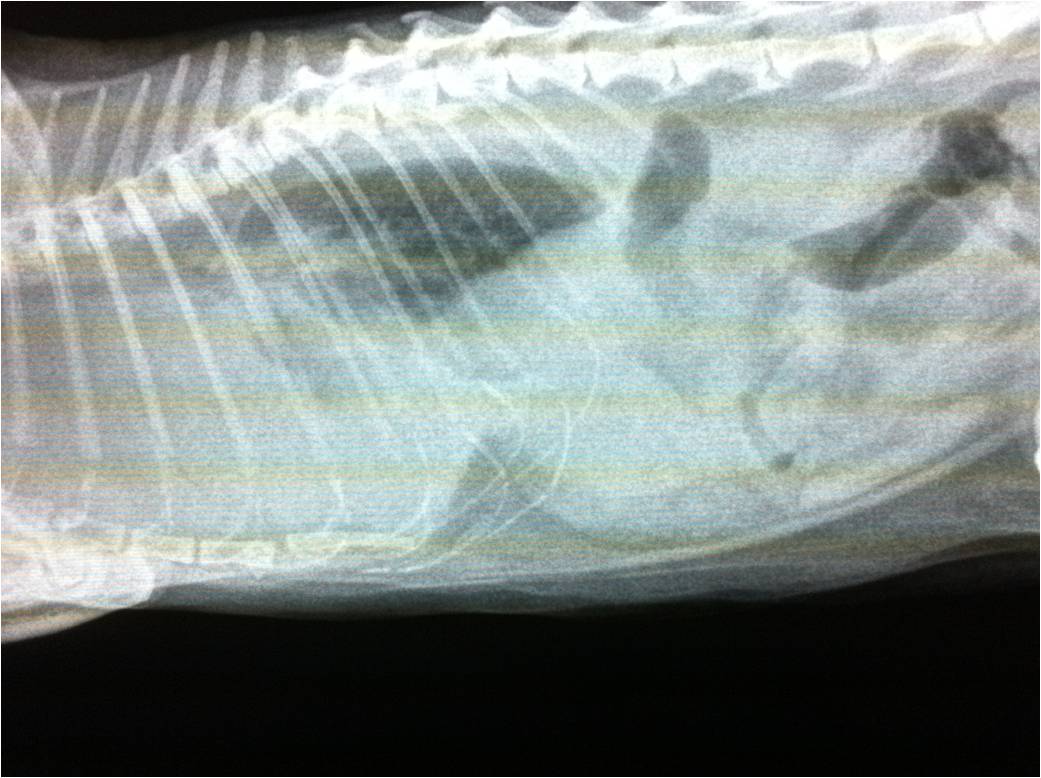

Photo 1 Radiographie Thoracique D Un Chat Atteint D Un Pyothorax Download Scientific Diagram